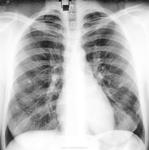

Сначала, в 11 году, был плотный очаг. К 2013 очевидно подрос, вполне может оказаться периферической опухолью.

На прямой р-грамме могут быть ретростернальные и парамаммарные регионарные л/у обеих молочных желез. Думаю: сначала в маммоцентр, потом КТ.

Если теоретически предположить, что плотная тень, видимая на прямой рентгенограмме - тень пара (ретро? интра?) маммарного (?) или ретростернального (?!!!) лимфоузла, патология которого обусловлена раком МЖ, возникает масса вопросов. 1. Почему столь жиденькая динамика метастаза (у молодой дамы!!!) за 2г? 2. Что все это время делает первичная опухоль? Ну, и в принципе: тень четко видна на боковом снимке, видно, что в легком. Нормальная современная тактика предложена во 2м посте. Но, конечно, обследовать МЖ никак не помешает)).

Создается впечатление, что тень не одна.Есть еще и справа и слева.

Петирфикат справа в S3 ( возможно в Sax )-если есть сомнения, возмите пациентку на R-скопию лёгких-определитесь с топографией изменённого участка ( имеет отношение к лёгочной ткани? какой сегмент ? и др.)

Периферический растет...

Девушка молодая,обидно пропустить патологию.Без сомнений,нечего гадать,надо делать РКТ.

Прямая и боковая разнятся (на мой взгляд) за счет суммации изображений обоих легких на боковой рентгенограмме. При всем уважении к линейной ТГ - в конкретном случае (молодая женщина, визуальный рост "очага", относительно малые его размеры, три года наблюдения, доверие клиницистов к КТ) сразу постарался бы найти возможность для КТ.

Обработанные снимки.